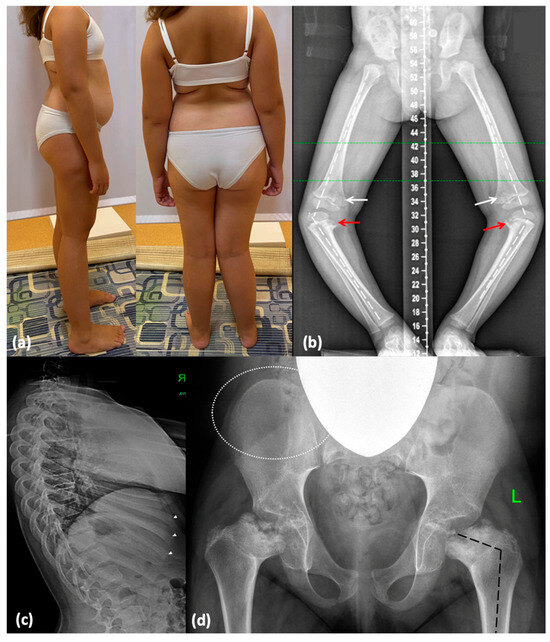

2.2.1. Family 1

| Referring diagnosis | Rickets-like disease, Blount disease, MED | Rickets-like disease, Blount disease, LCP disease, MED | LCP disease, MED | n/d | n/d |

| Irregular vertebral bodies | + | + | + | + | + |

| Platyspondyly | +/− | +/− | − | +/− | +/− |

| Lumbar hyperlordosis | + | + | − | + | − |

| Metaphyseal involvement | + | + | + | + | + |

| Delayed epiphyseal ossification | + | + | n/d | + | + |

| Proximal femoral epiphyseal involvement | + | + | + | + | + |

| Irregular iliac crests | +/− | +/− | n/d | − | n/d |

| Coxa vara | + | + | + | + | + |

| Genu varum | + | + | − | +/− | − |

| Hyperlaxity | + | + | − | n/d | − |

| Others | Equino-abducto-plano-valgus foot deformity, cervicothoracic kyphosis | Varus deviation of the right foot | − | Pectus carinatum (mild) | Mild pectus excavatum, thoracic kyphosis |

| Orthopedic surgery | Hemiepiphysiodesis | Hemiepiphysiodesis | − | No but planned for future | n/d |